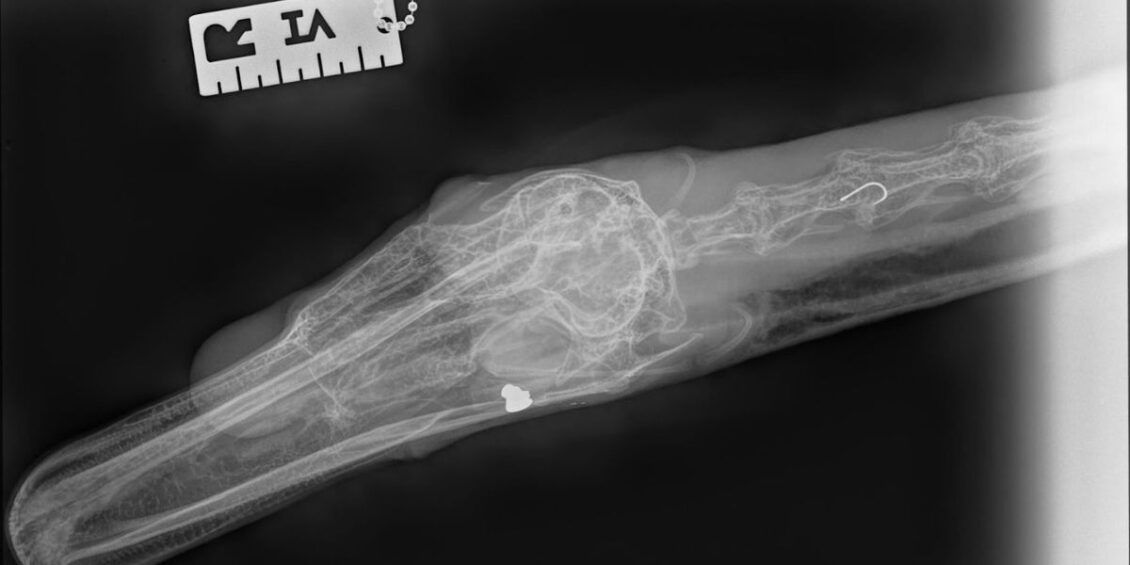

X-Rays on the male swan – found on Thursday 23 May in a pond in the Cefn Golau area in Tredegar – discovered a pellet in his head whilst investigating the fishing litter lodged down his neck. He had also been found with a fishing line around his leg.

Christine took the swan to a local vets for X-Rays where the hook and pellet were found, and then he was transferred to RSPCA West Hatch Wildlife Centre in Taunton for further investigations.